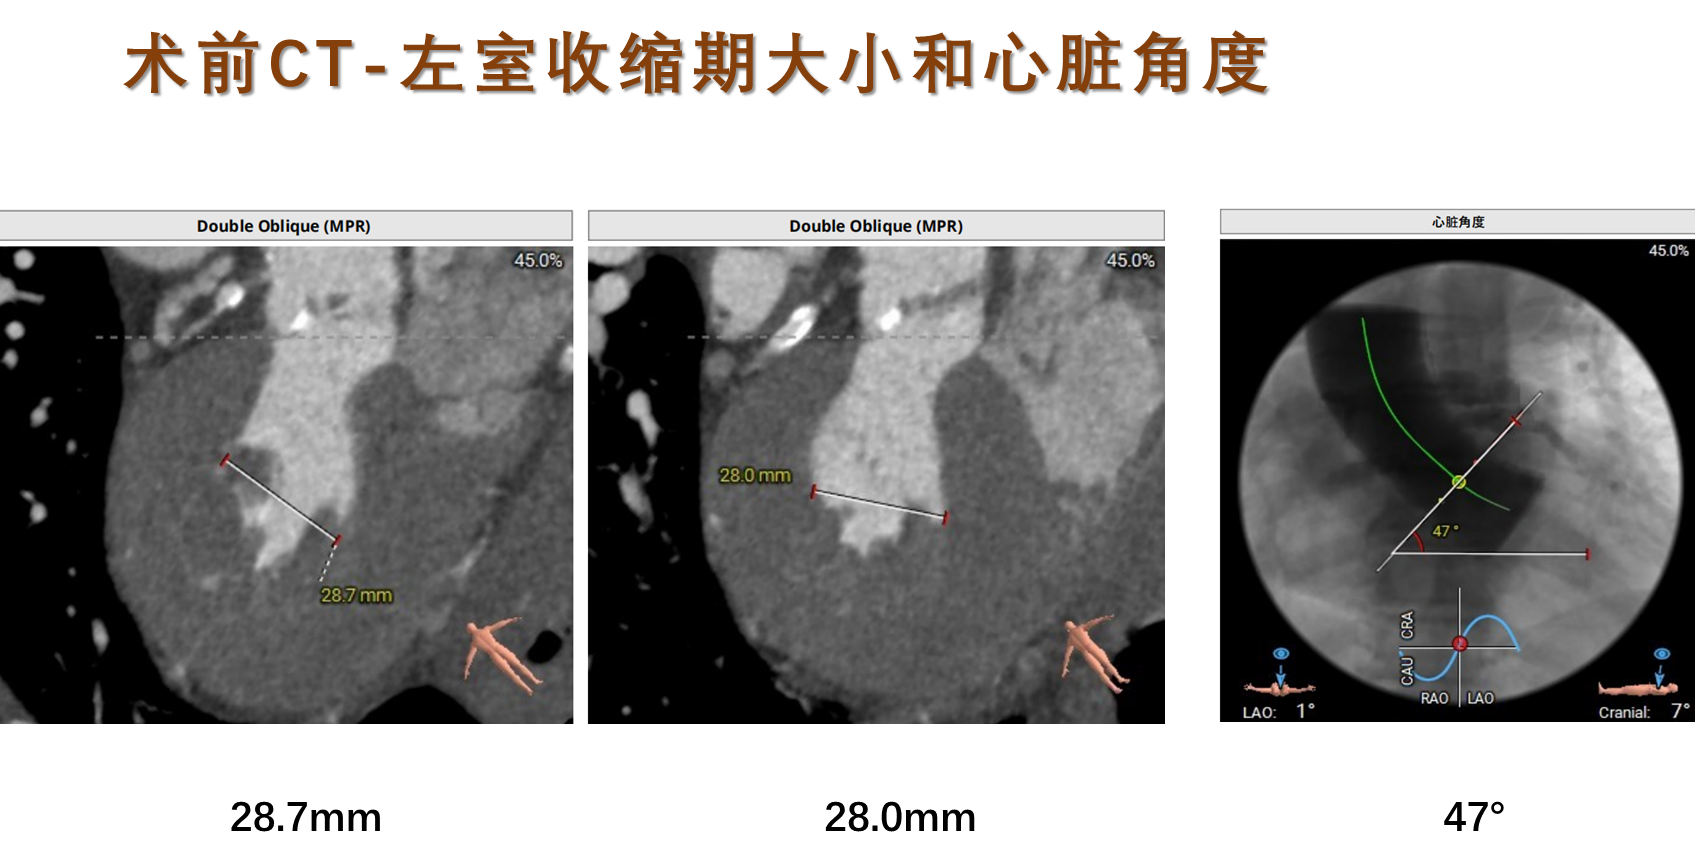

术前CT评估:

瓣膜选择:预装VenusA-Pro 23mm型号瓣膜,18mm球囊预扩,高位释放。